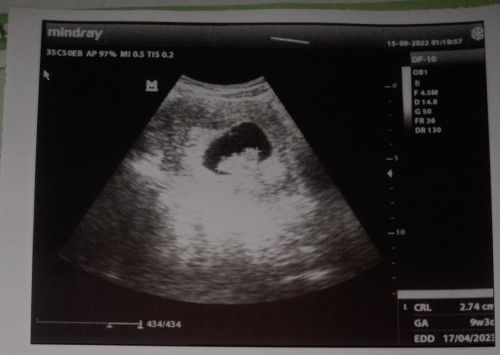

Baca lagiHai bund, bantu sharing yaa ☺️ Ini gambar usg TM1 awal2, jd baru terlihat kantung rahim dan janin yg masih sgt kecil. Alhamdulillah dr gambar itu janin udh di dalam kantong rahim. Ga diluar. Lalu cek bagian kanan. CRL itu istilah yang menunjukkan panjang jarak dari ujung kepala sampai ujung kaki janin.. utk EDD nya sendiri artinya perkiraan keterangan tentang perkiraan persalinan yang dihitung dari tanggal menstruasi semacam HPL gitu. Dan GA perkiraan usia kehamilan berdasarkan panjang tungkai lengan, kaki, dan diameter kepala janin. Utk lbh jelasnya, setiap kontrol siapin pertanyaan aja bund utk dr SpOG nya 🤗

Next kalo usg ditanyakan aja bund hehe Syg bgt soalnya udh bayar2 mahal Itu panjang janin 2,74cm usianyanya 9week3day terus hpl lahirannya 17april2023

panjang janin : 2,74cm usia kehamilan : 9minggu 3hari hpl : 17/04/2023